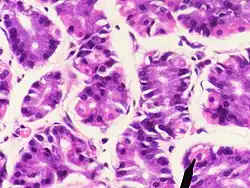

Parietalcelle

Parietalcellen (også kendt som oxyntic celle) er en celle, som befinder sig i mavesækkens slimhinde og er ansvarlig for sekretionen af saltsyre til blanding med ventrikelindholdet med formål at fordøje føden.

Cellen secernerer (udskiller) et HCl-holdigt sekret som også indeholder 'intrinsic factor', der hjælper med optaget af B12 vitamin senere i tarmen.